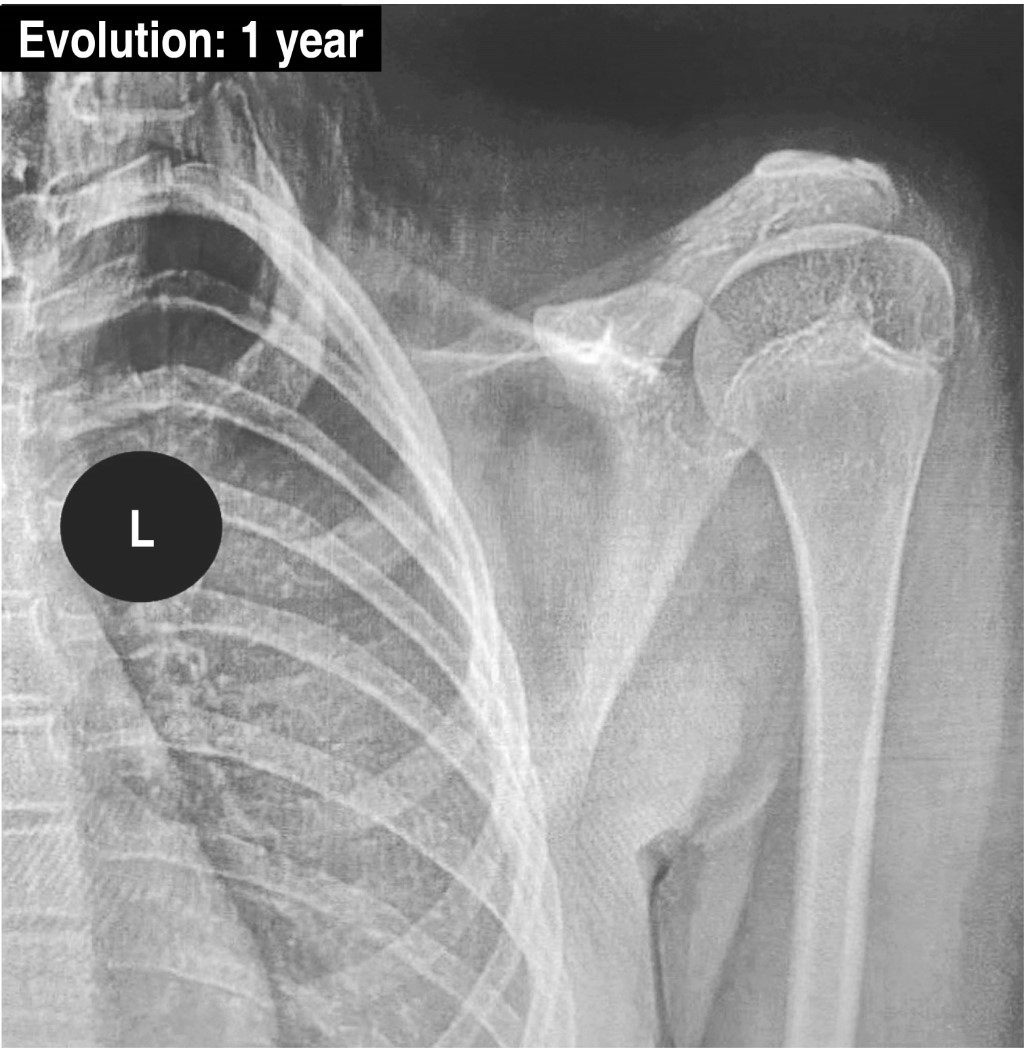

With one year of follow-up, the patient is asymptomatic, without clinical and imaging data of recurrence, and without functional limitation. Being a neoplastic clinical situation, the methodology to evaluate the functional postoperative result was through the Functional Score of the Musculoskeletal Tumor Society (MSTS score)28 that evaluates six domains scored on a 0 to 5 scale and transformed into an overall score ranging from 0 to 100% with higher score for better results: pain, functional activity, hand positioning, dexterity, lifting ability and emotional acceptance. Personal satisfaction and functional result, were completely satisfactory: 30/30 (Figure 5).

Figure 5